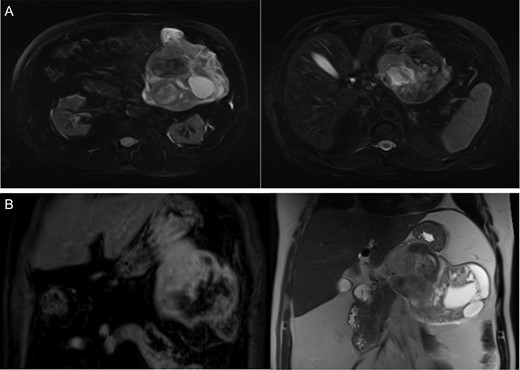

A 68-year-old male presented to the emergency department with vague complaints of right-sided flank pain. The patient had a history of nephrolithiasis and underwent a CT abdomen (Fig. 1A). The scan revealed a large heterogeneous mass in the left upper quadrant. Subsequently, an MRI was performed, confirming a 16 × 9 cm2 complex mass with both cystic and solid components (Fig. 1B). This appeared to extend from the gastric wall and resulted in mass effect on the pancreas; however, there was no evidence of lymphadenopathy or metastatic disease. While this lesion was difficult to definitively characterize by imaging studies, a diagnosis of mesenchymal origin tumor such as a GIST was initially preferred.

(A) CT abdomen demonstrates large heterogenous mass. (B) MRI coronal images display a heterogeneous mass on T1 (left) and T2 signal (right) arising from the submucosa with components restricting diffusion.